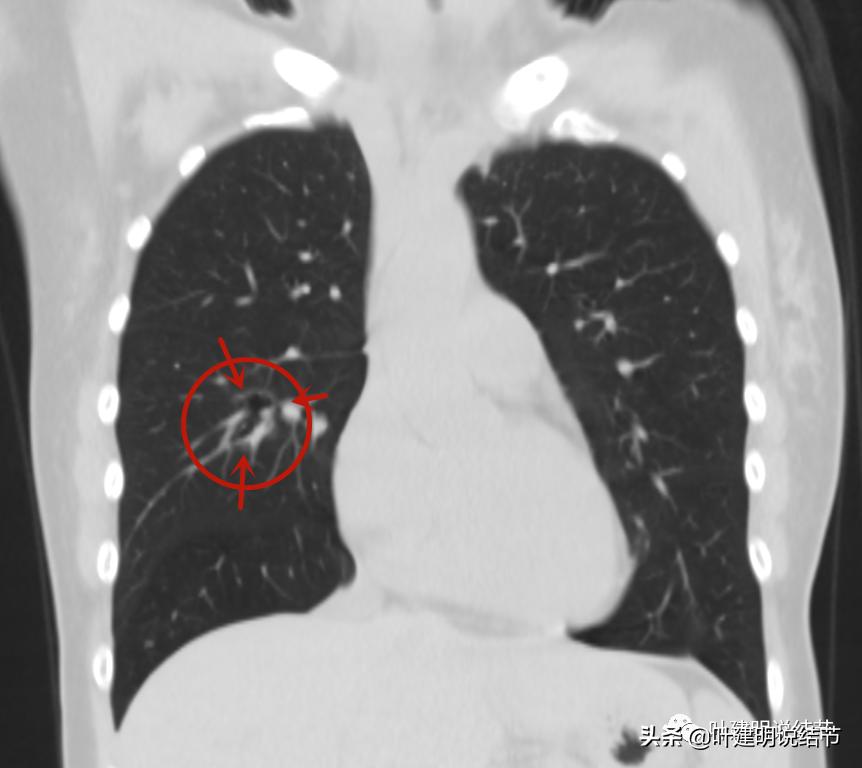

冠状位的影像提示囊腔型病灶,与血管没有间隙,囊壁略不均

矢状位见囊腔型病灶密度低,水平裂似略受牵拉,与血管之间没有间隙